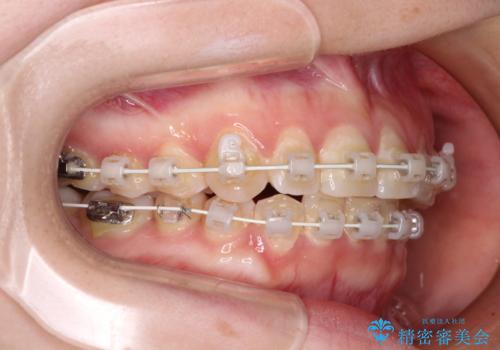

【モニター】前歯のデコボコを目立たないワイヤー装置で短期間矯正治療

- 上下前歯のデコボコを気にして来院された患者様です。

ワイヤー矯正でもインビザライン矯正でも対応可能でしたが、インビザラインでの自己管理の煩わしさを避けるため、ワイヤー装置にて矯正治療を行うこととしました。

患者様も驚く、僅か10か月での治療終了となりました。

下顎前歯が1歯欠損しているため、上下正中は合わず、左右奥歯の咬み合わせは理想的とはならない仕上がりとなります。